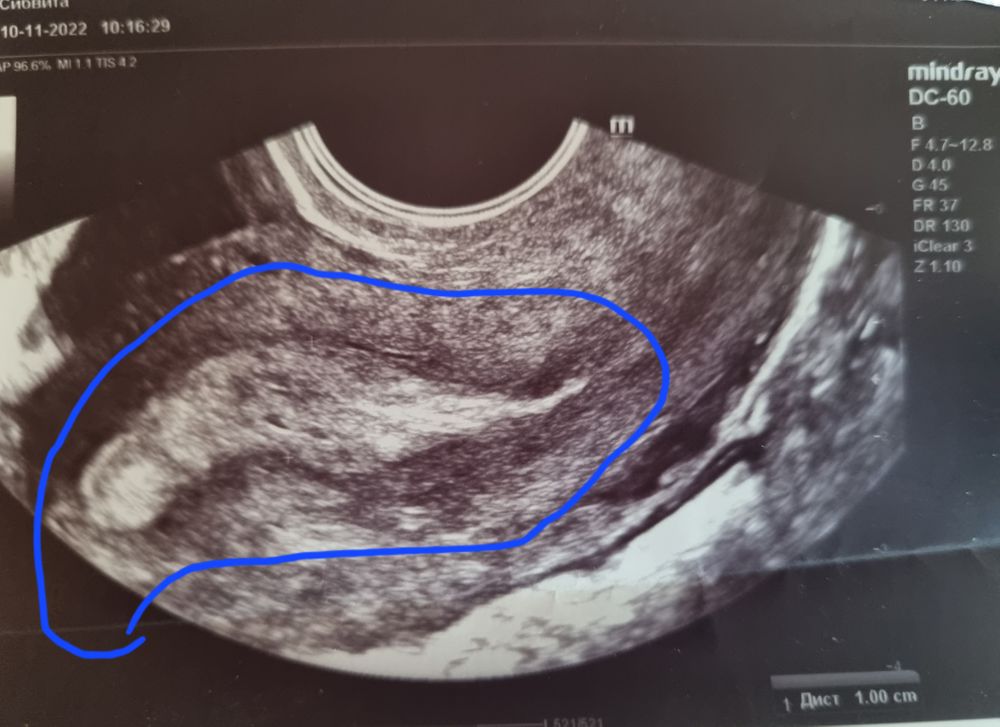

Месячный циклДелала узи на 42 цикл, у меня он 32, врач не чего не сказал и не объяснил, сегодня уже 45 день цикла. А месячных так и нету. И что такое, где я синим обвела ?

Эндометрий очень неоднородный на 1 фото. 2 фото желтое тело скорее всего. 3 киста фолликулярная. Дюфастон допивайте, на отмене придут месячные. На 5-7 день цикла я бы эндометрий пересмотрела на предмет полипов. Нехорошо выглядит он у вас

Обведен синим эндометрий. Он у вас прям очень неоднородный, похоже, будто месячные вот-вот пойдут